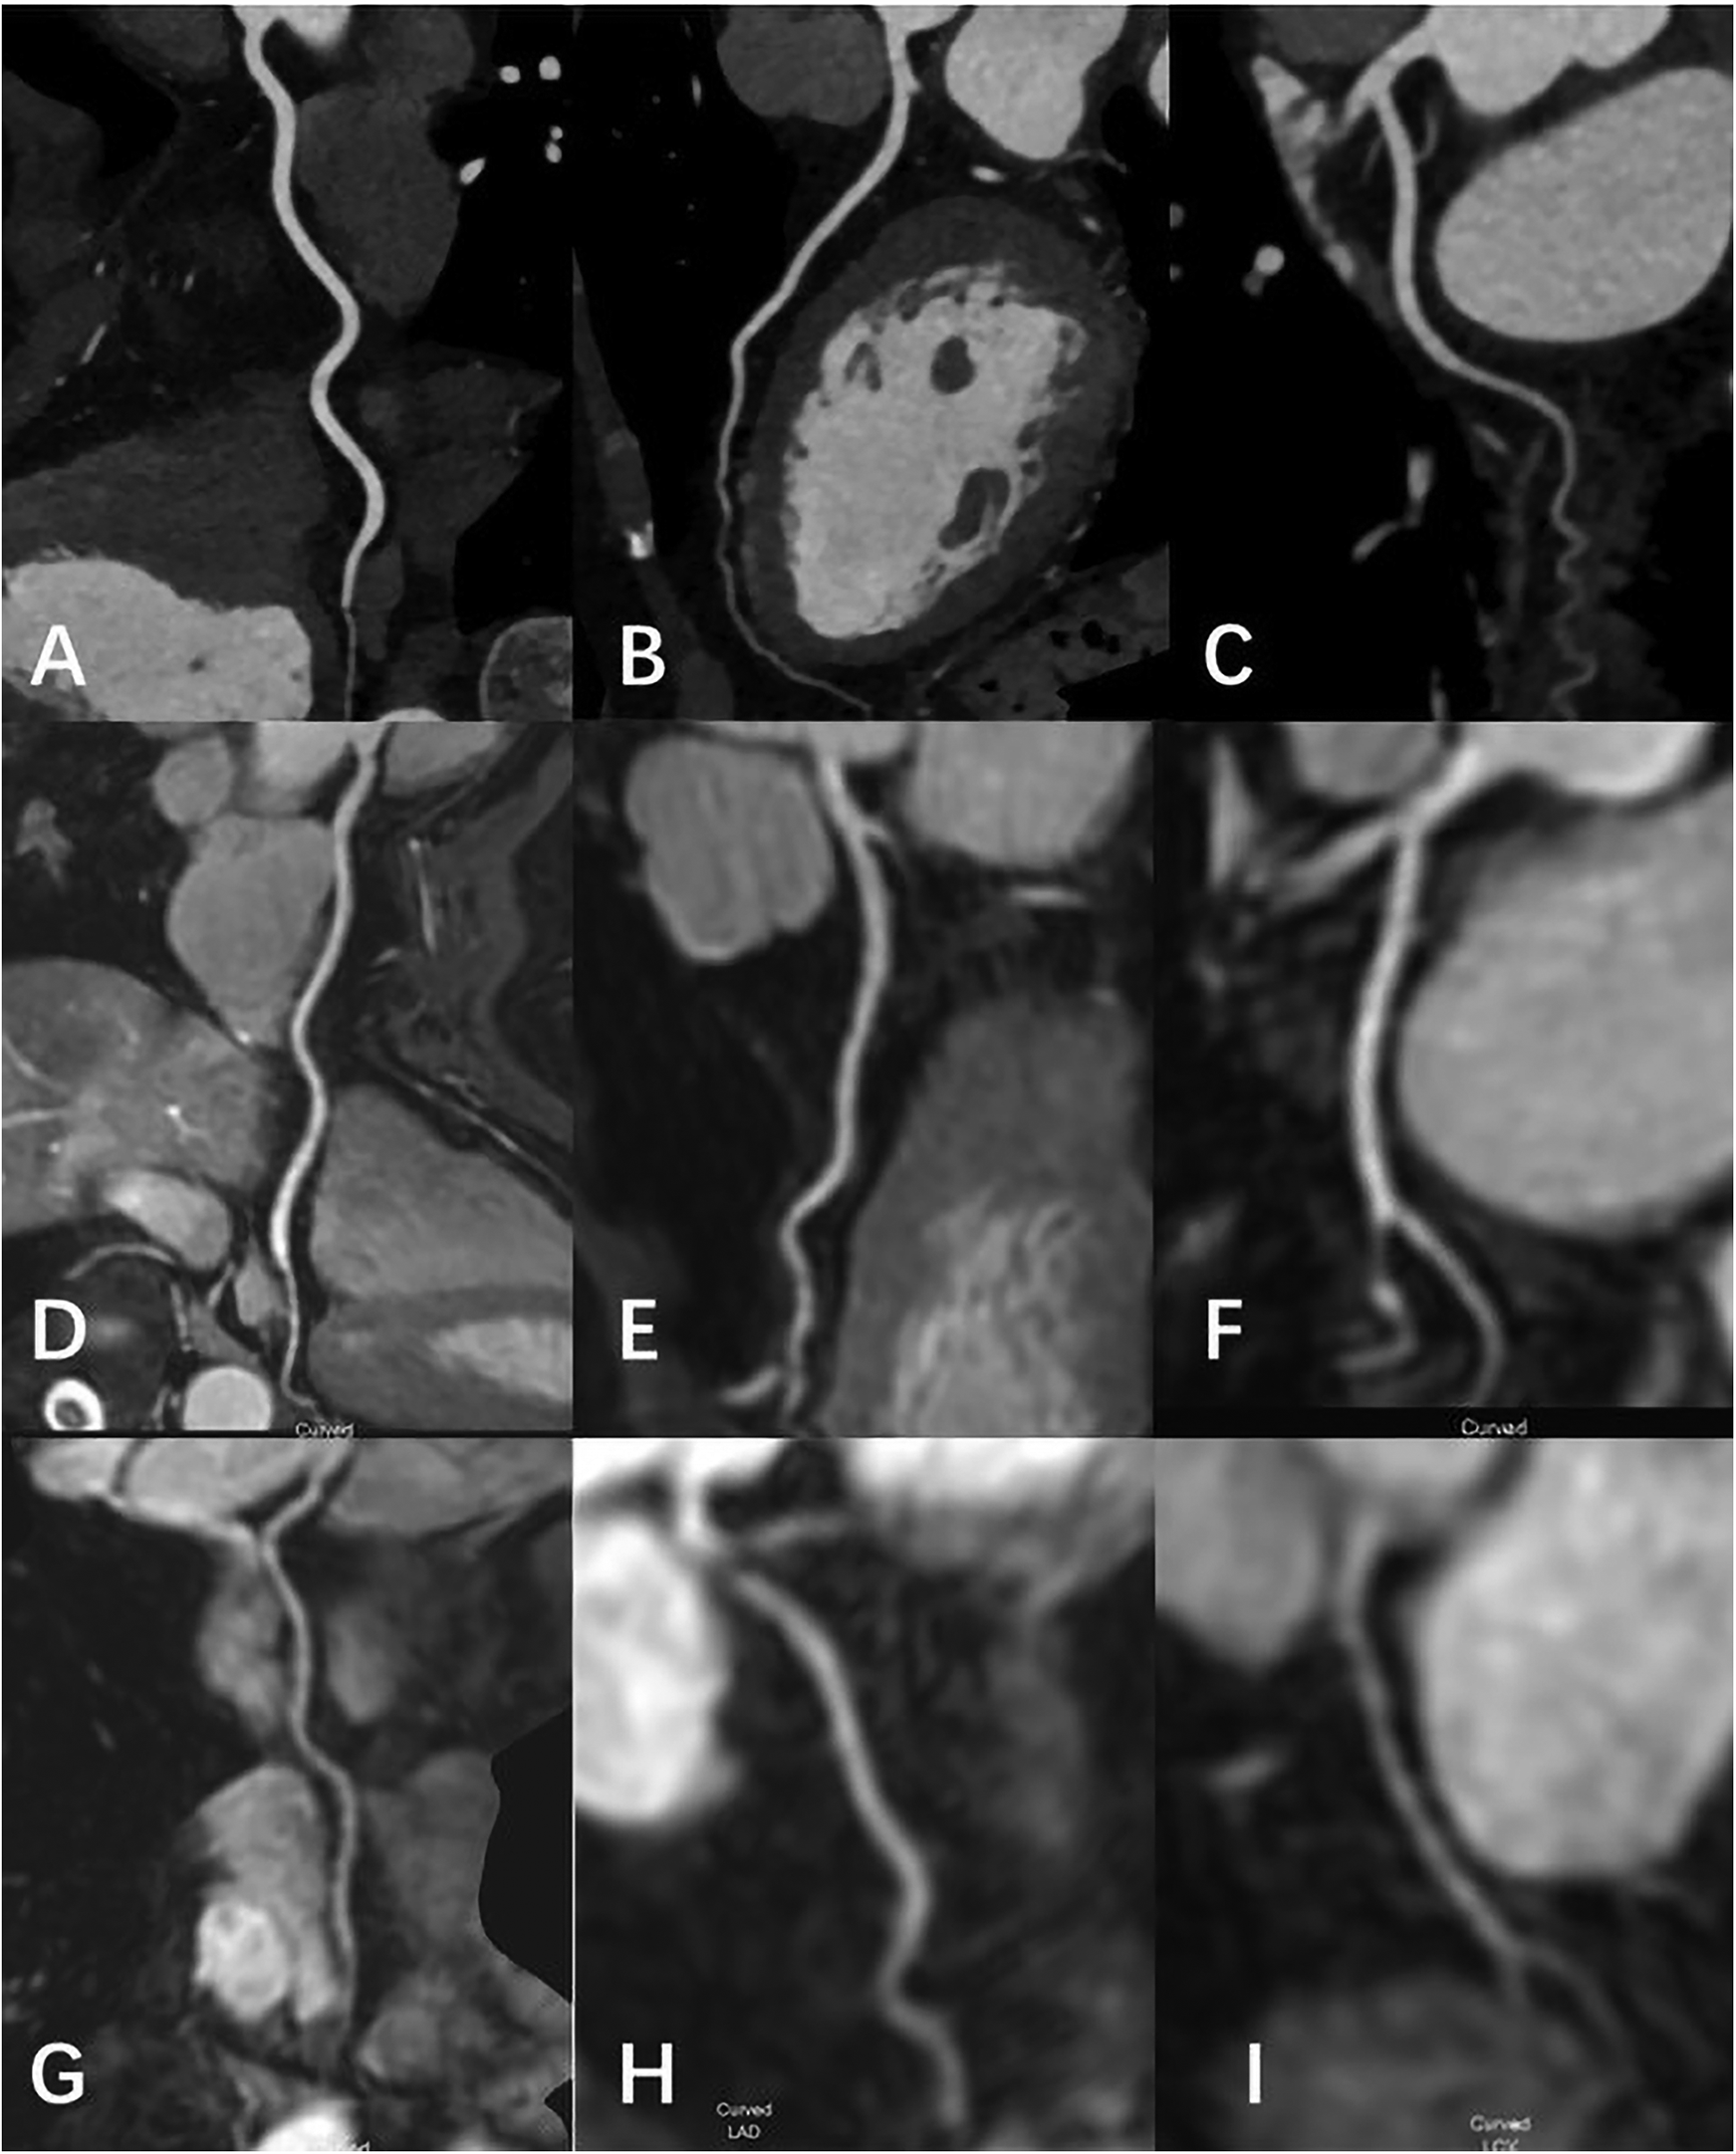

Figure 4

Female, 69 Y, with chest pain. (A–C) The RCA, LAD, LCX shown in coronary CTA, coronary artery stenosis was not observed; (D-F) the RCA, LAD, LCX shown in 3D-BTFE sequence, the lumen edges were sharp, the coronary arteries were clearly delineated, and the subjective images scored 5; (G–I) the RCA, LAD, LCX shown in MSG-EPI sequence, and the subjective images scored 4.